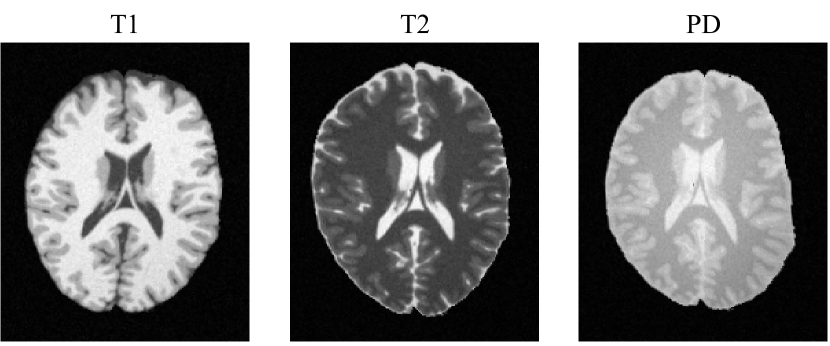

Data description. The BrainWeb online database111https://brainweb.bic.mni.mcgill.ca/ provides simulated T1-, T2- and PD-weighted MRI volumes from an anatomical phantom. The image volumes have the physical spacing of 181×217×181mm3181217181superscriptmm3181\times 217\times 181\,\text{mm}^{3}. We used the image volumes corrupted by 3%percent33\% noise (relative to a reference tissue) and 20%percent2020\% intensity non-uniformity. The data were preprocessed by skull-stripping and the anatomical labels were remapped into foreground regions composed of cerebrospinal fluid (CSF), grey matter (GM), and white matter (WM). For a proof of concept, we only selected the middle slice from the axial view of each image for demonstration. The images were normalized by z-scoring for a fair comparison between different methods.

3. 3.

Recovery of initial misalignment. Since the simulated images were aligned by design, one could apply initial spatial transformations to the images and correct the misalignment through unbiased groupwise registration. Readers are referred to Sec. 2.1 of the supplementary materials for details on how to generate the initial misalignments.

We used multi-level isotropic FFDs as the transformation model to recover spatial correspondences from the initial misalignment. The FFD spacings and the number of registration steps are described in the supplementary material. The deformation regularization was imposed by bending energy over the FFD meshes, with λ=0.001𝜆0.001\lambda=0.001. The Adam optimizer [42] was adopted to optimize the registration, with an initial step size of η=0.1𝜂0.1\eta=0.1.